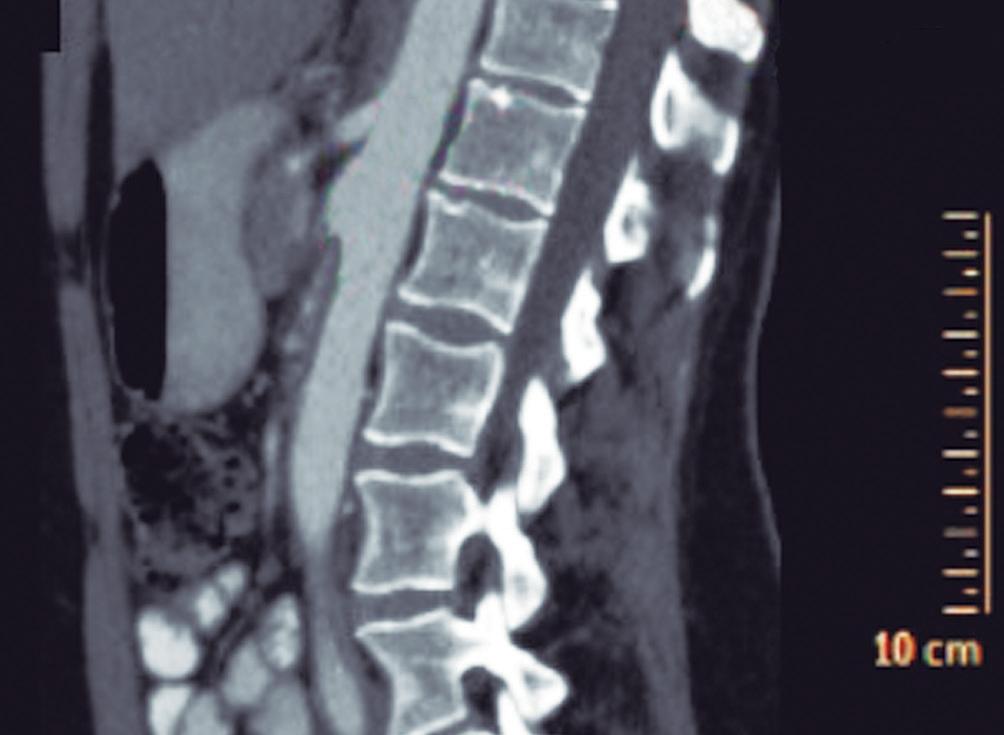

CASOS CLÍNICOS Biopsia guiada por ecoendoscopía como herramienta diagnóstica mínimamente invasiva para metástasis mesorrectal de carcinoma de células claras renales: reporte de caso

Nicole Marie Kahn, Mayra Florencia Defanti, Yanina Gabriela Carlino